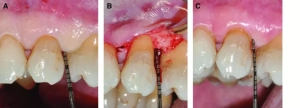

Residual Probing Depth and Periodontitis Grading Good Predictors of Tooth Loss Due to Periodontitis

Residual Probing Depth and Periodontitis Grading Good Predictors…